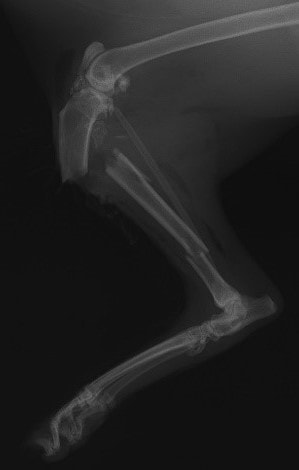

症例3:キルシュナーワイヤーのピンニングによる整復

ペルシャ猫 11ヶ月齢 雄

他院にて左大腿骨遠位の成長板骨折(salter-harrisⅠ型)が認められており、治療相談を目的として来院。当院にて、キルシュナーワイヤーを用いたピンニングにより骨折部位の整復を行いました。術後の経過は良好で、現在も経過観察中です。

術前レントゲン

術後レントゲン